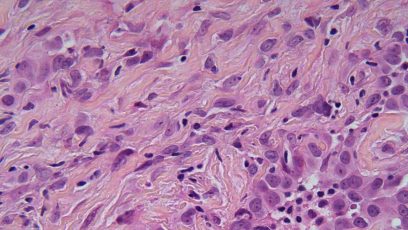

WCLC2020: Opløftende data for patienter med recidiverende malign mesotheliom

Hør Jens Benn Sørensen perspektivere resultaterne fra CONFIRM-studiet, der viser interessante data for behandling med nivolumab monoterapi til patienter med recidiverende malign mesotheliom.